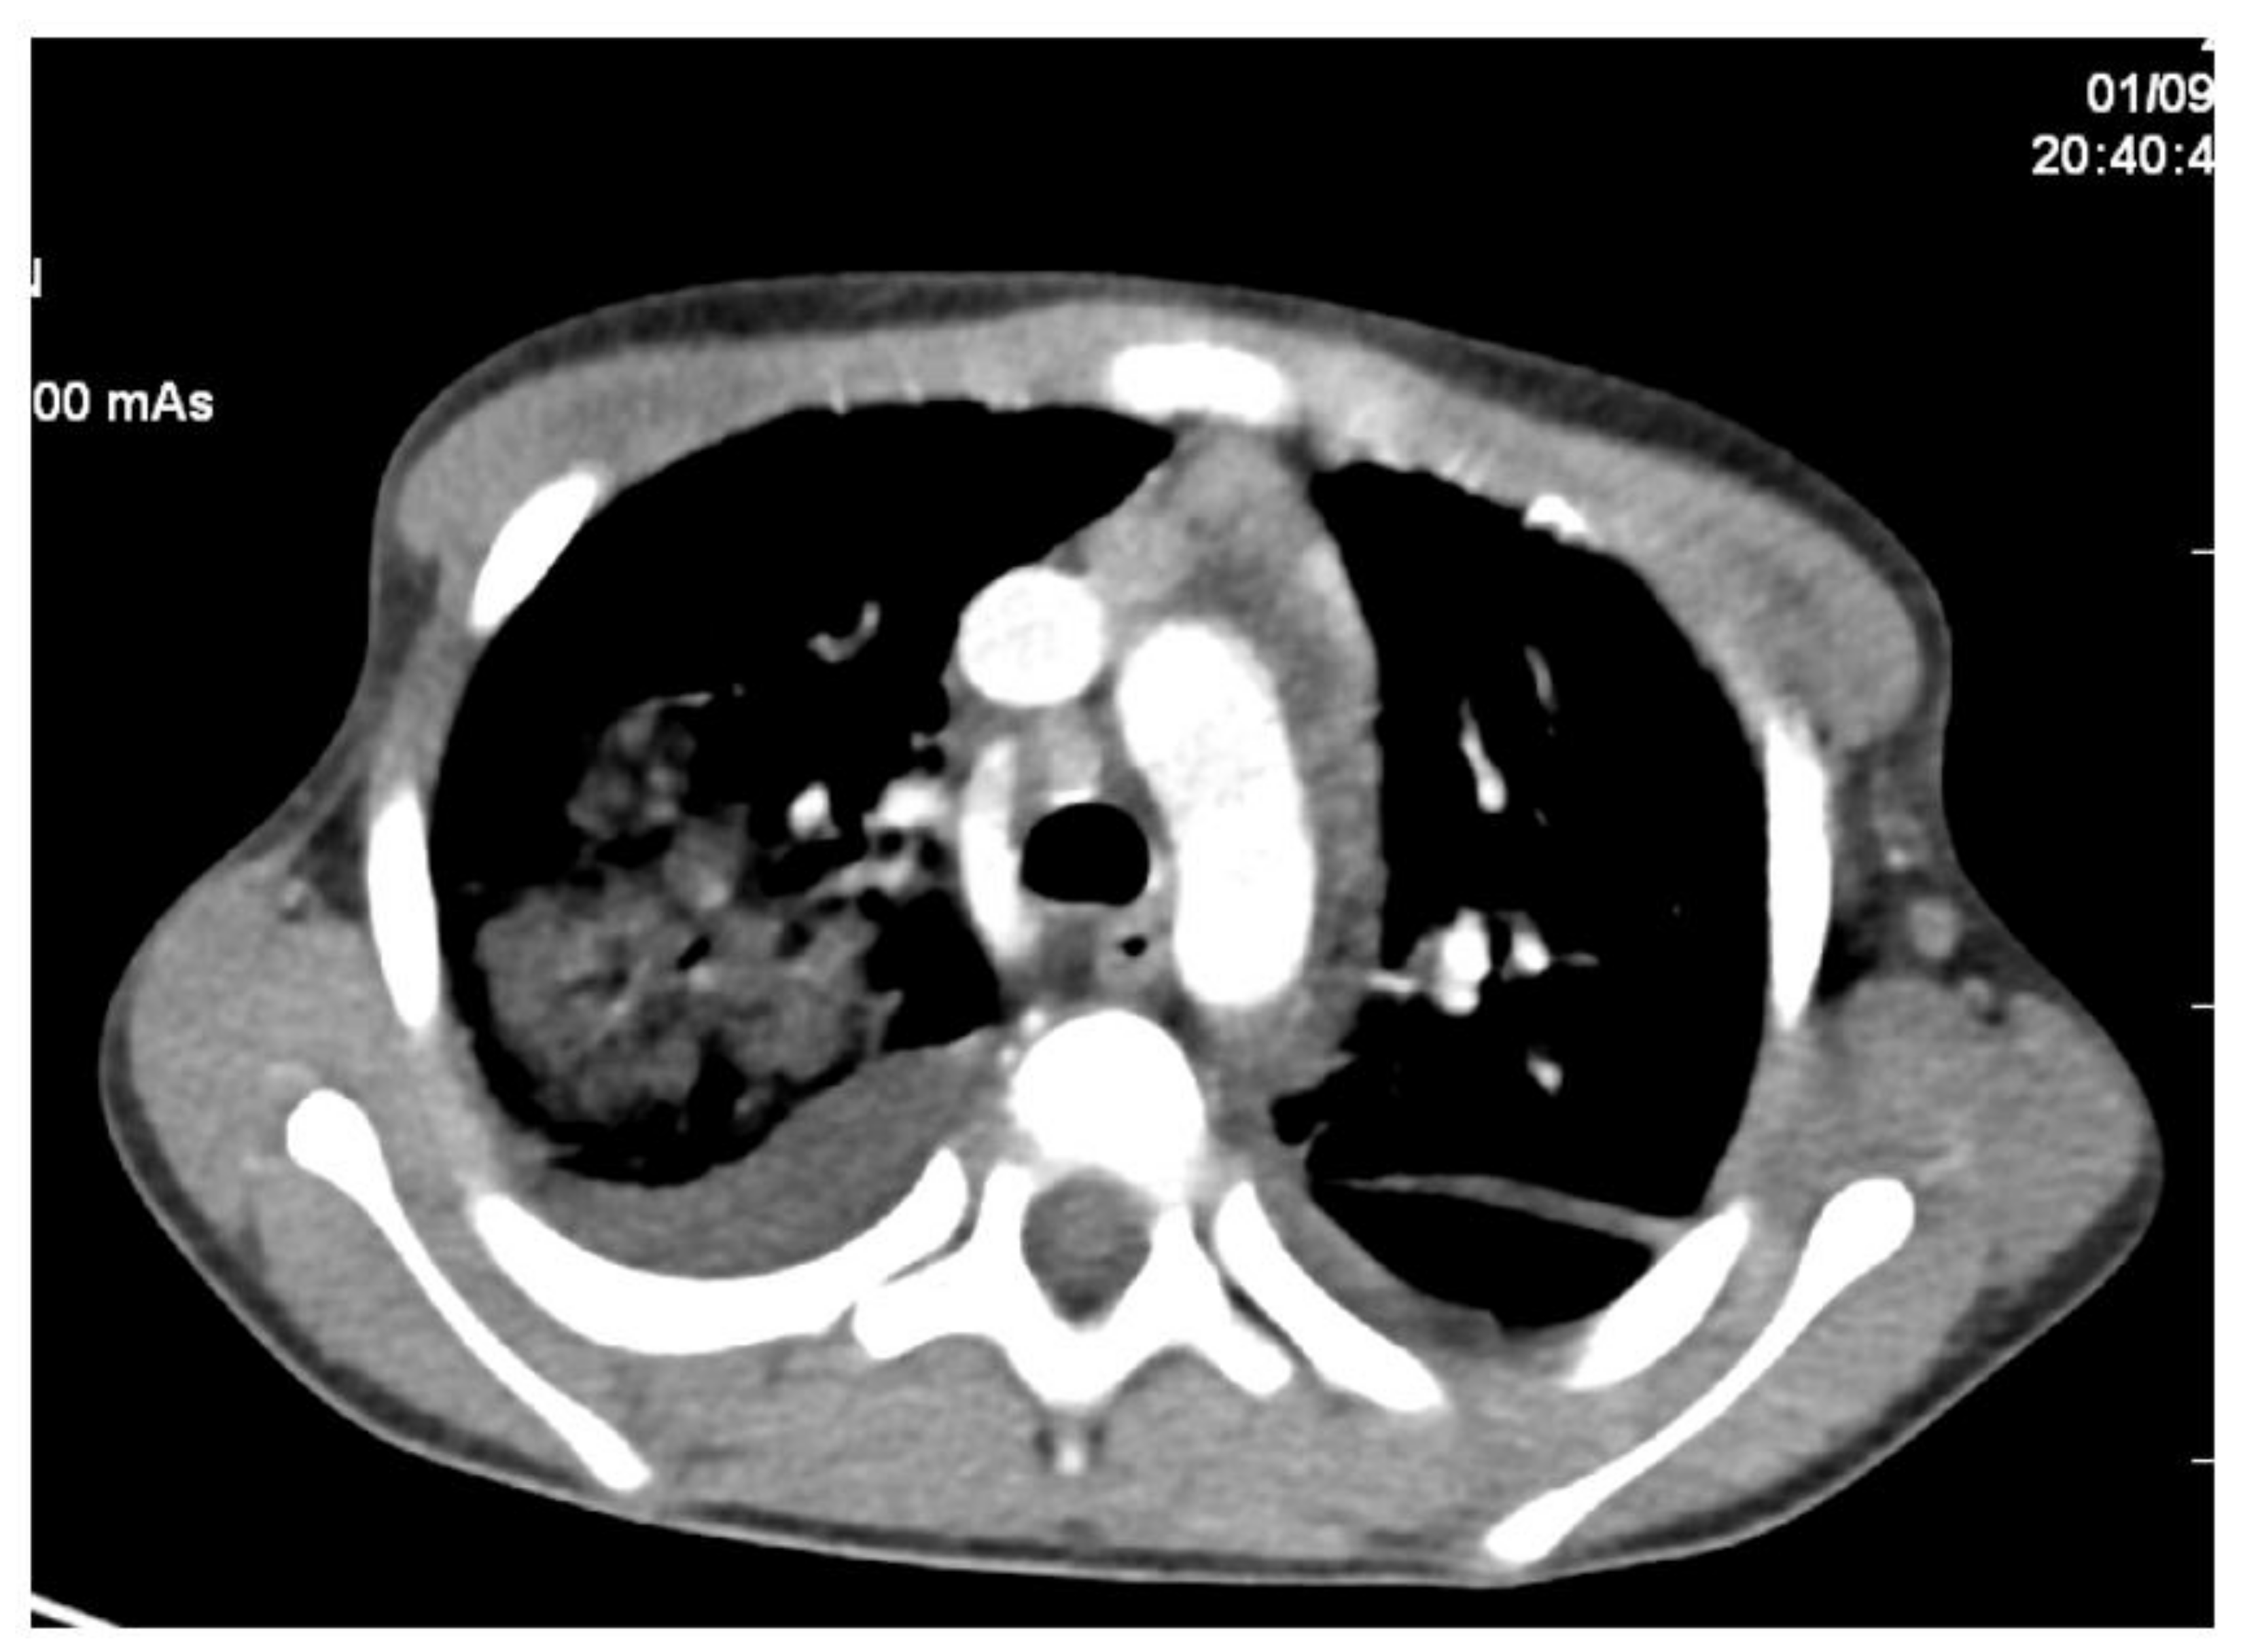

2. Case Report